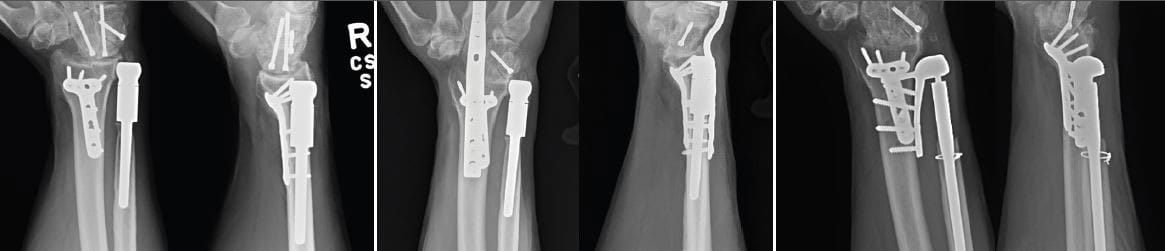

In fall 2015, Dr. Malone did a total wrist fusion due to continued pain and progressive post-traumatic arthritis of the man’s wrist joint. Following the surgery, the man was not able to move his wrist up and down or side to side, but he could rotate his forearm through the radioulnar joint. The procedure relieved some of the patient’s pain, but he still had sharp discomfort with twisting maneuvers.

During the surgery, Dr. Malone removed the previously placed ulnar head implant as well as the wrist fusion plate. With the new, three-component implant device, he first used screws to attach a plate to the radius along the ulnar aspect. He placed a second component within the medullary canal of the ulna. He then connected the two with a third portion, which restored kinematics of the radial ulnar joint.

The patient now has full rotation of his forearm, full range of motion in his hand and significant resolution of his pain.